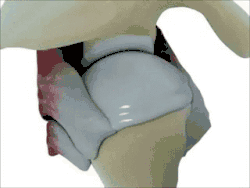

The shoulder joint (or glenohumeral joint from Greek glene, eyeball, + -oid, 'form of', + Latin humerus, shoulder) is structurally classified as a synovial ball-and-socket joint and functionally as a diarthrosis and multiaxial joint. It involves an articulation between the glenoid fossa of the scapula (shoulder blade) and the head of the humerus (upper arm bone). Due to the very loose joint capsule, it gives a limited interface of the humerus and scapula, it is the most mobile joint of the human body.

Structure

The shoulder joint is a ball-and-socket joint between the scapula and the humerus. The socket of the glenoid fossa of the scapula is itself quite shallow, but it is made deeper by the addition of the glenoid labrum. The glenoid labrum is a ring of cartilaginous fibre attached to the circumference of the cavity. This ring is continuous with the tendon of the biceps brachii above.